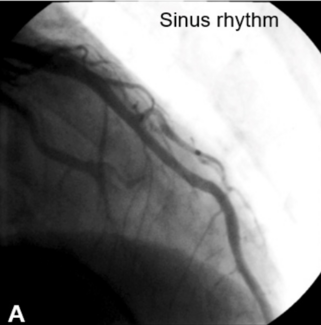

A 52-year-old man presented acutely with inferior ST-segment elevation myocardial infarction (STEMI). The left coronary system was unobstructed.